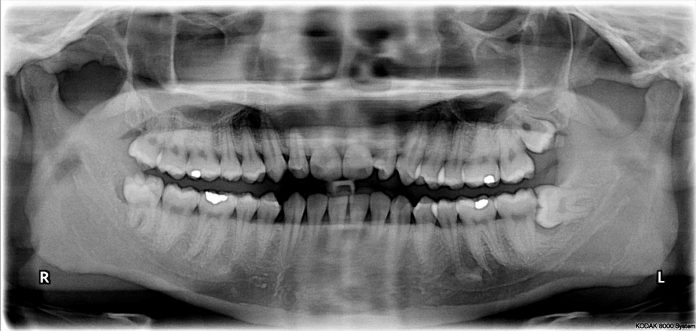

Wisdom teeth are the most posterior of all molars, residing in the far back corners of your mouth. They can emerge at any time, typically between 17 and 25, and often affect surrounding teeth as they come in. During a trip to the dentist, an X-ray can show how the teeth are growing and if they are growing at an angle under the gum line. If deemed necessary, your dentist will often make an appointment to have the teeth surgically removed. However, sometimes a dentist is not necessary in determining that it is time to part with your wisdom teeth. Here are some signs to look for:

When the wisdom teeth grow in under the back teeth, it can cause the teeth to shift. This can cause pressure on the other teeth in the area and create a crowding situation in the mouth. This crowding can change the appearance of the entire line of teeth whether they are on the top or the bottom. If you have had braces or extensive dental work, then the shifting could negate any part of the work that has been done. Another thing to consider is the timing of the eruption of the wisdom teeth. Some dentists will go ahead and remove the teeth as soon as they appear so that they don’t cause damage to the other teeth later on in life.